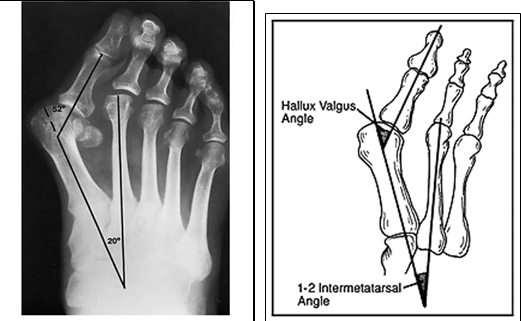

What is hallux valgus?

Deformity in which there is medial deviation of the 1st metatarsal and lateral deviation +/- rotation of the hallux with associated joint subluxation

What investigations are done if you suspect hallux valgus?

Plain radiographs (AP, lat & oblique- weight bearing) to help assess severity

We can measure the degree of lateral deviation of hallux; measure angle between first metatarsal & first proximal phalanx. What is a normal angle?

<15 degrees